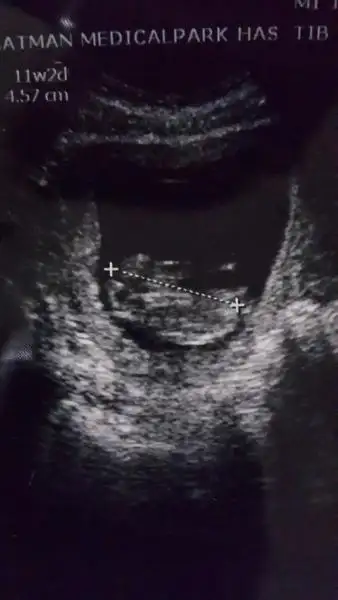

Eki Görüntüle 473831 simdi burada cikintilara bakin eger bel popo cizgisine paralel ise kiz

yok 30 derecelik bir aciyla yukari bakiyorsa erkek

yabancilarin hepsi biliyor bunu biz neden eksik kalalim gayet bilimsel simdi ellerinde11 12 13 ultrason fotografi olanlar alsin hemen baksin yada koyalim buraya yorumlayalim